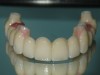

Fig 4. A CAD/CAM milled framework served as foundation for the mandibular restoration.

Figure 4